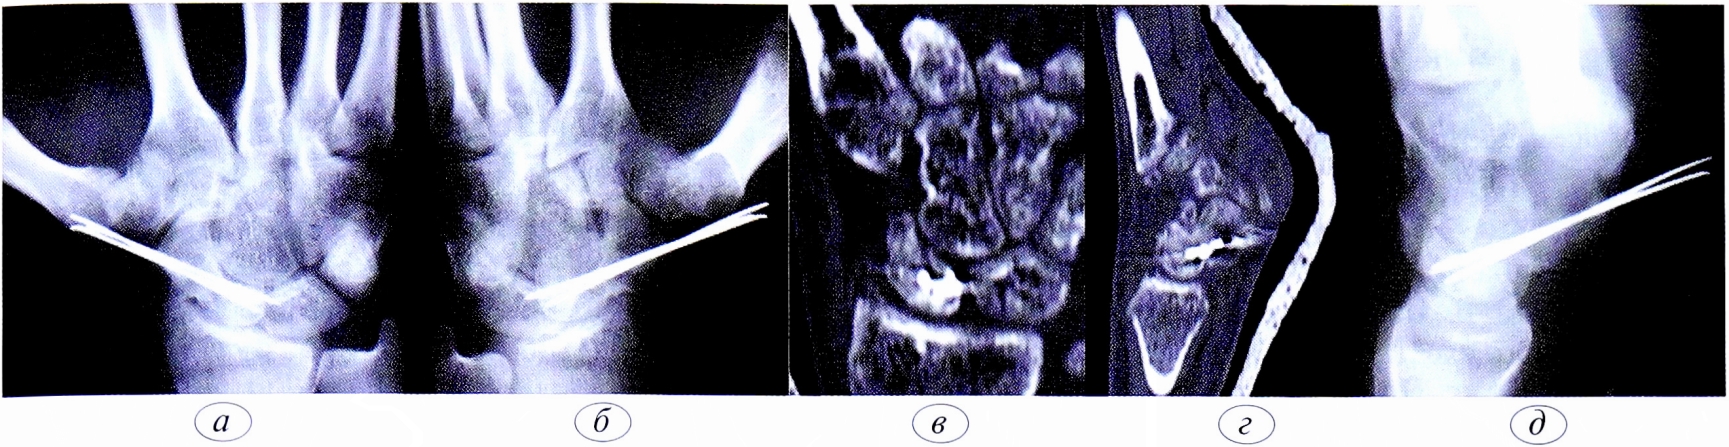

Функция пальцев полная. Сила кулачного схвата правой (доминантной) кисти — 22 кг, снижена почти в 2 раза по сравнению с нормой. Сила схвата левой кисти — 40 кг. Оценка по шкале ВАШ — 3 балла, по опроснику DASH — 21,16 балла. На рентгенограмме (рис. 5, а, б, в) и при компьютерной томографии выявлен ложный сустав ладьевидной кости (см. рис. 6, г).

Рис. 6. Пациент К.,19 лет. Диагноз: ложный сустав ладьевидной кости правой кисти. а — рентгенограмма в прямой проекции; б — рентгенограмма в ¾; в — рентгенограмма в боковой проекции; г — компьютерная томография.

Fig. 6. Patient К.,19 years. Diagnosis: pseudarthrosis of the scaphoid of the right hand. a — straight projection x-ray; b — ¾ projection x-ray; c — lateral projection x-ray; d — computed tomography.

Рис. 7. Пациент К.,19 лет. Диагноз: ложный сустав ладьевидной кости правой кисти. Через 8 нед после операции, а — рентгенограмма в прямой проекции; б — рентгенограмма в ¾; в — рентгенограмма в боковой проекции; г — компьютерная томография, сагиттальная проекция; д — компьютерная томография, аксиальная проекция.

Fig. 7. Patient К.,19 years. Diagnosis: pseudarthrosis of the scaphoid of the right hand. 8 weeks after surgery. a — x-ray in straight projection; b — x-ray in ¾; c — x-ray in a lateral projection; g — computed tomography, sagittal projection, d — computed tomography, axial projection.

Пациенту были выполнены артроскопическая резекция ложного сустава ладьевидной кости, костная пластика измельченным губчатым трансплантатом из крыла подвздошной кости, остеосинтез ладьевидной кости 3 спицами.

Через 8 нед после операции, по данным лучевой диагностики/рентгенограммы и компьютерной томографии (рис. 9, а, б, в), сращение было достигнуто. Спицы удалили.